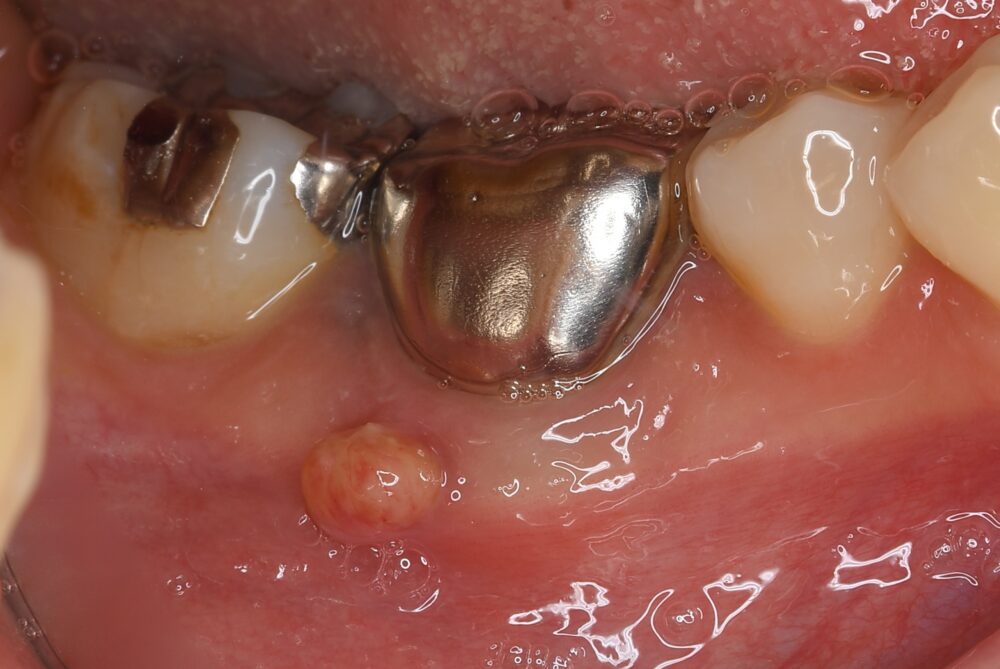

症例1:パーフォレーションリペア症例

(歯の中に大きな穴が空いてしまっているのを埋めて再生を促す治療)

歯に穴が空いていて骨に炎症がある状態 |

CTでも歯の周囲に骨がないのが分かる。 |

BEFORE |

人為的根穿孔を起こした部分に感染を起こしており、歯周ポケットが9㎜ありました。 ラバーダム防湿とマイクロスコープを使用して丁寧に治療を行いました。 殺菌性があり歯を補強することのできるMTAという根管充填材料を使用して、歯周ポケットは2㎜に改善しました。 |